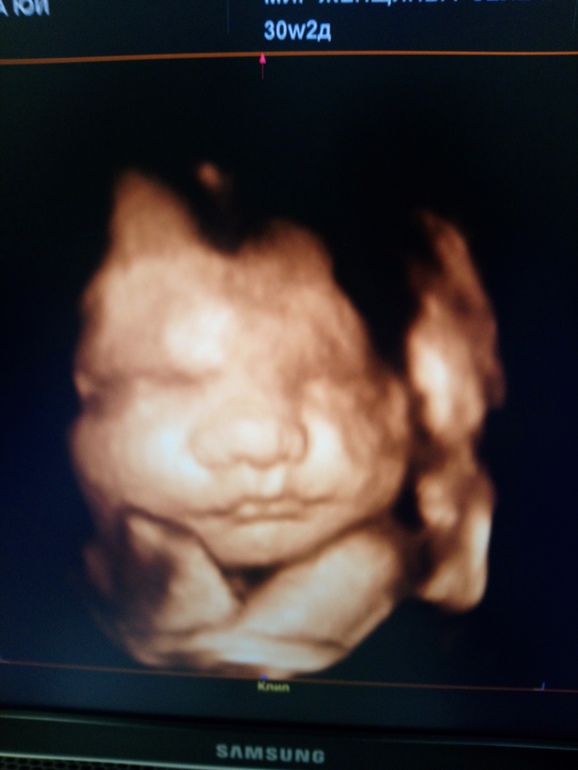

утолщение мвп. Да и сама плацента 38мм, степень зрелости 1. Но сказали, на это не смотреть, а смотреть кровотоки. А они в норме. Сын щекан. 1500гр. Наконец-то дал более менее сфоткать лицо.. Все в плаценту прячется и кулаками закрывается)

Ну, и вот собственно он - царевич наш)